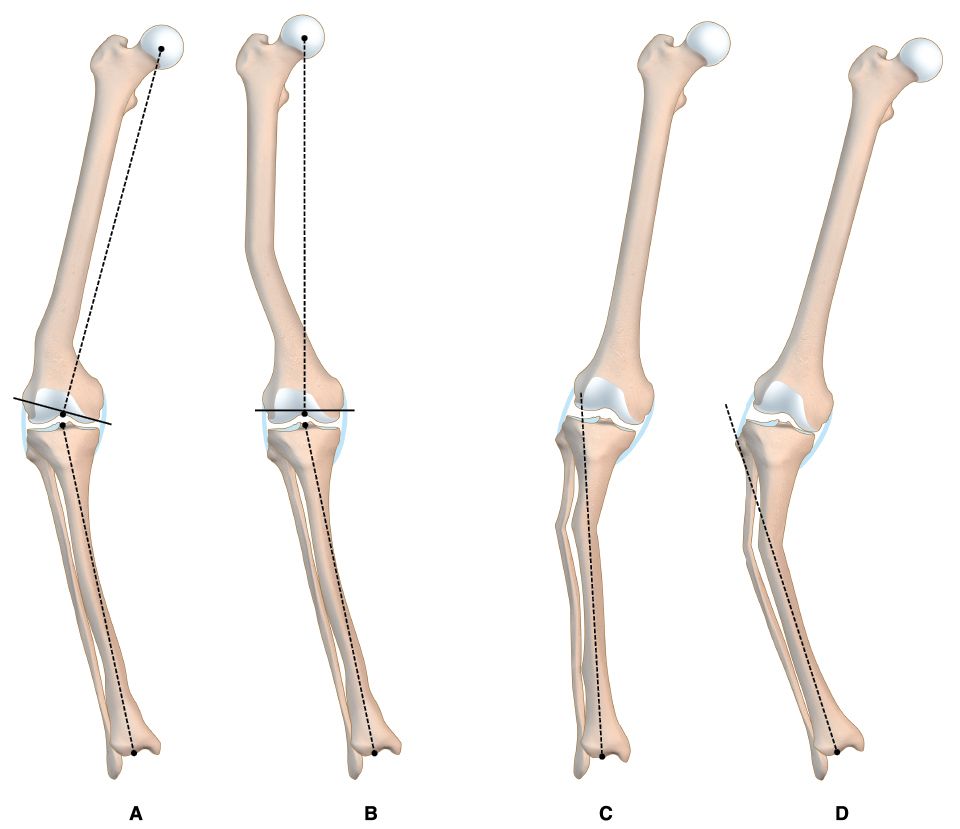

This issue's clinical contributions span alignment strategies and implant selection in major joint reconstruction. In total knee arthroplasty, one article examines TKA in extraarticular deformities managed through intraarticular correction without increased constraint, while a second introduces inverse kinematic alignment as a framework for personalized alignment. Shoulder arthroplasty is addressed through an assessment of the stemless shoulder implant. A further study evaluates whether surgical approach influences canal fill of the femoral component in THA, contributing to the evidence base on technique-dependent outcomes.